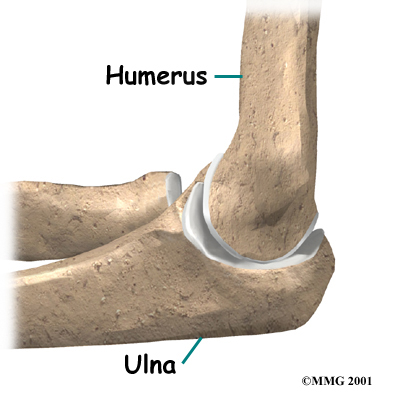

Bones and Joints

The bones of the elbow are the humerus (the upper arm bone), the ulna (the larger bone of the forearm, on the opposite side of the thumb), and the radius (the smaller bone of the forearm on the same side as the thumb). The elbow itself is essentially a hinge joint, meaning it bends and straightens like a hinge. There is a second joint that makes up the elbow, where the end of the radius (the radial head), meets the humerus.

The bones of the elbow are the humerus (the upper arm bone), the ulna (the larger bone of the forearm, on the opposite side of the thumb), and the radius (the smaller bone of the forearm on the same side as the thumb). The elbow itself is essentially a hinge joint, meaning it bends and straightens like a hinge. There is a second joint that makes up the elbow, where the end of the radius (the radial head), meets the humerus.

This joint is complicated because the radius has to rotate so that you can turn your hand palm up and palm down. At the same time, it has to slide against the end of the humerus as the elbow bends and straightens. This part of the elbow is even more complex because the radius also joins with the ulna to form a joint, and this part of the radius has to slide against the ulna as it rotates the wrist as well. The end of the radius at the elbow is shaped like a smooth knob with a smooth cup at the end to fit on the end of the humerus. The edges are also smooth where it glides against the ulna.

Articular cartilage is the material that covers the ends of the bones of any joint. Articular cartilage can be up to one-quarter of an inch thick in the large, weight-bearing joints. It is a bit thinner in joints such as the elbow, which don't support weight. Articular cartilage is white, shiny, slippery, and has a rubbery consistency.

The function of articular cartilage is to absorb shock and provide an extremely smooth surface to make motion easier. It allows joint surfaces to slide against one another without causing any damage. We have articular cartilage essentially everywhere that two bony surfaces move against one another, or articulate. In the elbow, articular cartilage covers the end of the humerus, the end of the radius, and the end of the ulna.